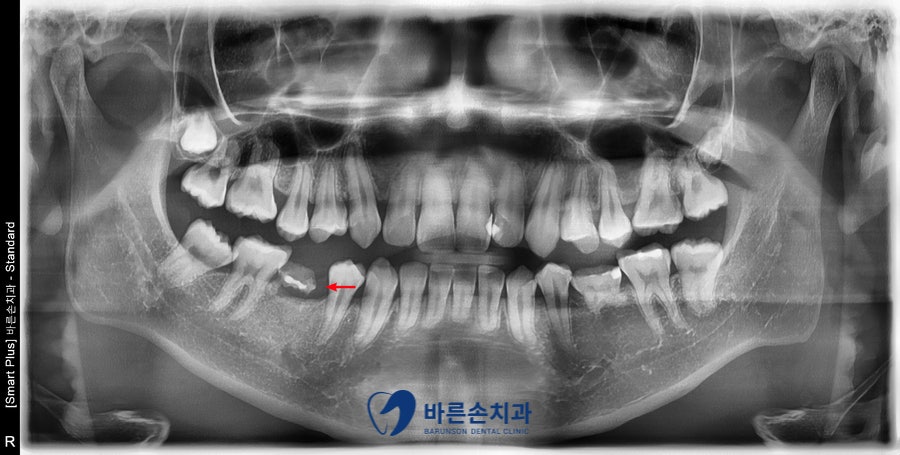

정확히 보기 위해 파노라마 엑스레이 사진을 찍었는데요.

빨간색 화살표 부분을 보시면

유치가 깨져서 일부가 남아있고,

후속 영구치가 없는 것을 확인 할 수가 있습니다.

유치의 뿌리도 다 녹아서 거의 남아있지 않으므로,

치료를 해서 쓸 수가 없는 상황인데요.